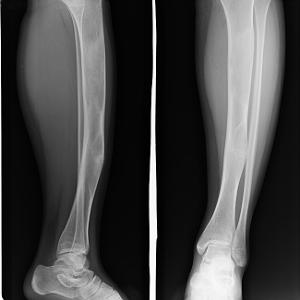

骨纤维异常增殖症是一种病因不明、缓慢进展的自限性良性骨纤维组织疾病。正常骨组织被吸收,而代之以均质梭形细胞的纤维组织和发育不良的网状骨骨小梁,可能系网状骨未成熟期骨成熟停滞,开出生后网状骨支持紊乱,或构成骨的间质分化不良所致。